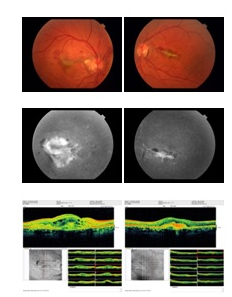

Six eyes of 4 patients with CNV due to angioid streaks were enrolled. In all cases, diagnosis of pseudoxanthoma elasticum was depended on skin biopsy. Eyes with any presumed signs of AMD were excluded. The off-label use of the drug and its potential risks were discussed with all patients, and informed consent was obtained from all cases. Patients’s data like age, gender, medical history, ocular symptoms and history, duration of the disease (CNV), prior ocular treatment, interval between the last treatment and the first injection of bevacizumab, and association with PXE (biopsy proven) was recorded. All patients underwent a complete medical examination by an internist to identify potential systemic disease associated with angioid streaks. Detailed ophthalmic evaluation including best corrected visual acuity (BCVA) with standard Snellen chart, slit lamp biomicroscopic examination, fundus photography, fundus fluorescein angiography (FFA) and macular scanning with optical coherence tomography (OCT) was performed prior to the initial injection (Figure 1). Central macular thickness was measured using spectral domain OCT (Optovue RTVue software version 3.5, Optovue Inc., Fremont, CA). Best corrected visual acuity measurements were based on the logarithm of the minimal angle of resolution (logMAR) scale.

Figure 1 Before anti VEGF injection: Fundus photograph of patient 1 showing choroidal neovascular membrane due to angioid streaks. Fluorescein angiography shows classic subfoveal choroidal neovascular membrane with leakage. OCT shows subretinal edema.